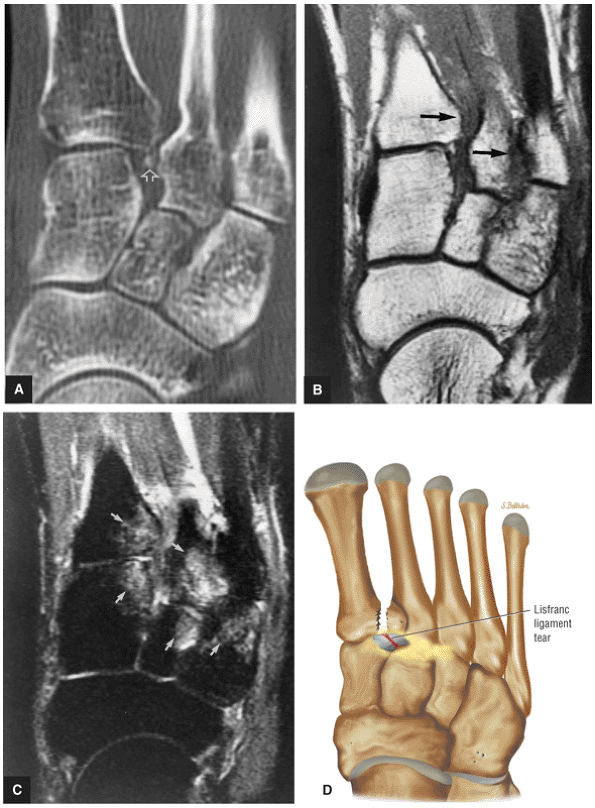

![]() |

FIGURE 5.28 Tibiotalar Joint.

|

FIGURE 5.29 Impingement.

FIGURE 5.30 Subtalar Facets.

FIGURE 5.31 Tarsal Joints.

FIGURE 5.32 Hindfoot.